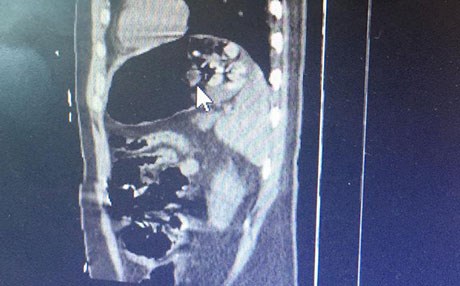

Düzenlenen operasyonla yakalanan zanlının, çekilen MR sonucu midesinde 15 paket olduğu tespit edildi.